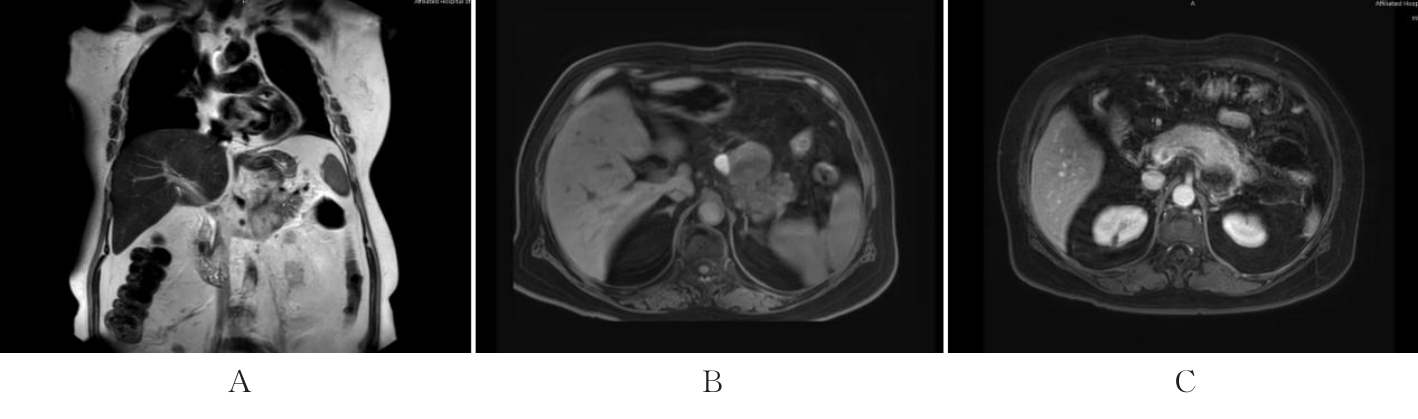

Switch/sucrose non-fermentable (SWI/SNF)-related matrix-associated actin-dependent regulator of chromatin subfamily B member 1 (SMARCB1)/integrase interactor 1 (INI1) (SMARCB1/INI1)-deficient undifferentiated pancreatic carcinoma (UPC) is an extremely rare special type of pancreatic cancer. This article reported the clinical manifestations, auxiliary examinations, diagnosis, and treatment of a patient with SMARCB1/INI1-deficient UPC, and reviewed the relevant literature. The patient, a 65-year-old female, was admitted due to intermittent upper abdominal pain for more than one month, aggravated with nausea and vomiting for 9 d. The abdominal CT scan performed at another hospital suggested a pancreatic space-occupying lesion. The physical examination results on admission revealed upper abdominal tenderness, without rebound tenderness or muscle guarding. The laboratory tests results showed a carbohydrate antigen 199 (CA199) level of 50.58 U·mL-1 and a fasting blood glucose level of 9.98 mmol·L-1. The abdominal MRI results revealed a mixed cystic and solid abnormal signal in the pancreatic body and tail, showing irregular extraluminal protrusion; it appeared as a slightly hypointense signal on T1-weighted imaging (T1WI), with the hemorrhagic part of the tumor appearing hyperintense; it appeared as a hyperintense signal on T2-weighted imaging (T2WI) with unclear boundaries, measuring 2.0-5.6 cm, causing compression and invasion of the gastric wall; enhanced scanning showed obvious rim enhancement of the tumor capsule, invasion of the splenic artery and vein, and portal vein thrombus formation. The gastroscope results revealed a 4.0 cm×5.0 cm mucosal elevation on the greater curvature of the gastric body, considered to be caused by compression from the pancreatic mass. The clinical diagnosis was a pancreatic space-occupying lesion, highly suspected to be malignant, with surgical resection being the preferred treatment option. The postoperative pathological diagnosis was SMARCB1/INI1-deficient UPC with a small component of moderately differentiated squamous cell carcinoma. The patient received chemotherapy after surgery and has been followed up for 5 months, with an improved quality of life compared to before surgery, no significant discomfort, and remains under close follow-up. SMARCB1/INI1-deficient UPC is relatively rare, with non?specific clinical manifestations, usually progressing rapidly and associated with a poor prognosis; therefore, early diagnosis and treatment should be pursued in clinical practice.